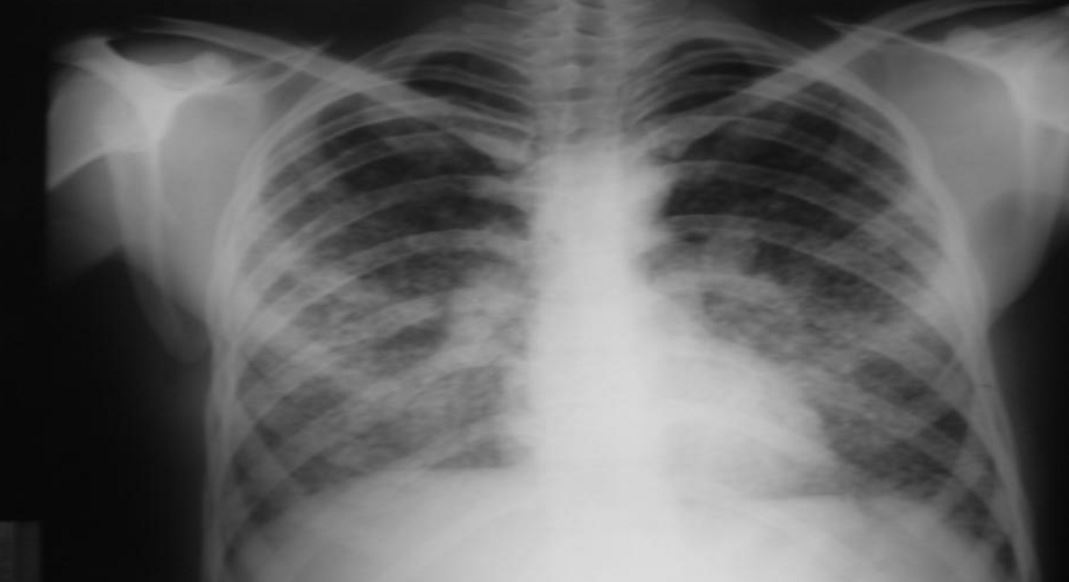

Yapılan araştırmalarda Pulmoner Emboli hastalarının otopsi sonuçlarına göre analizler vermektedir. Bu analizlere göre hastaların büyük çoğunluğu hastalık belirti vermeden kendiliğinden iyileşir ya da teşhis edilemeden düzelir. Bundan da anlayabileceğimiz gibi hasta şikayet duymadan bu hastalık ile yaşayabilir. Pulmoner embolisi bazı hastalıklar ile karıştırılabilir özellikle zatürre, kronik bronşit hastalıkları gibi. Bir çeşit testler ve görüntüleme yöntemleri sayesinde ( elektrokardiyografi, göğüs radyografisi, anjiyografi, MR görüntüleri, arter kan gazları) yapılan tetkikler sayesinde Pulmoner Emboli teşhis edilebilir. Bu sayede diğer hastalıklardan da ayırt edilmiş olacaktır.